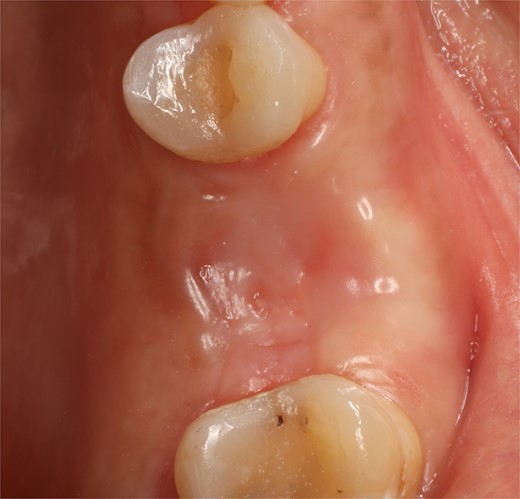

Following local anesthesia, an intrasulcural incision was made from the distal surface of the premolar, continuing through the sulcus to the mesial surface of the second molar in the vestibular and palatal surfaces. After the molar was extracted, granulation tissue was observed inside the socket that continued inside the maxillary sinus (Fig. 3); The socket was scaled, washed, and rinsed with physiological saline. The labial and palatal mucoperiosteal flaps are raised with full-thickness tunneling of the tissue, exposing the labial and palatal bone plates to allow a space for the ribose-crosslinked collagen membrane that will be used for socket closure. A 5 mm × 10 mm × 10 mm collagen sponge with hydroxyapatite and ribose was used, which was taken to the alveolus without hydration so that it absorbs as much blood as possible. It is important that the sponge has retention in the alveolus so that it does not displace within the maxillary sinus and is positioned at the same level as the remaining bone crest. A collagen membrane crosslinked with ribose was placed from buccal to palatal under the tunneled tissues (Fig. 4). A 5–0 absorbable monofilament suture was used, another layer of the collagen membrane was used in the occlusal area that was exposed, and two horizontal mattresses were sutured to give stability to the biomaterials (Fig. 5).